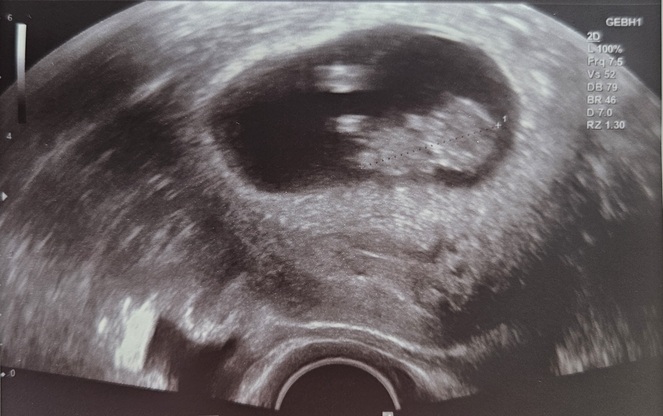

"Du wirst Oma/Opa/Onkel/Tante" - Tagebücher aus der Schwangerschaft von Marie aus bei Heidelberg